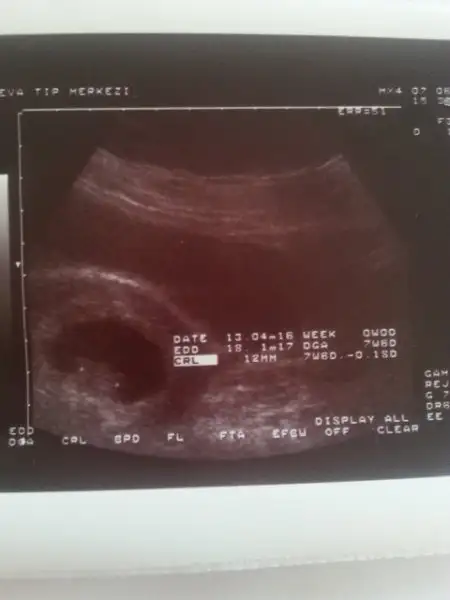

Bebeğin kesedi konumu teorisi tuttum canım sağlıkla kucaklaTahmini olan var mi acaba ? :)

Havalianne__ . bana da yorum yapar mısın 8 ve 12 haftalık goruntuler.Karından usg ikisi de

6+0 vajinal 8+0 karından 8+2 vajinal

Eki Görüntüle 1847341 bu bebegimin 9 haftalik usg resimi... :) burda ne gibi?